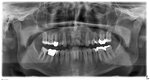

Ich hab alle Ärzte durch, Blutbild ok, LTT auf Allergie ok. Zahnärzte meinen OPG ist in Ordnung. Aber H. D. sandte mir das OPG zurück mit "4 Riesen Eiterherde" +Riechnerv Tumor? Lt. Dr. Schüler Eitergifte um die toten Zähne, welche ins Gehirn weitergewandert sind. Festzustellen ist, dass ich extrem geruchsempfindlich geworden bin und die beiden OPGs von 2010 und 2011 eine Änderung der Nasenaufnahme deutlich zeigen. (weißer Schweif).

Sieht man auf dem OPG Eiter bzw. eine Riechnervvergiftung?

Anbei 3 OPGs und eine Bewertung von Dr. D.

Ich hab alle Ärzte durch, Blutbild ok, LTT auf Allergie ok. Zahnärzte meinen OPG ist in Ordnung. Aber H. D. sandte mir das OPG zurück mit "4 Riesen Eiterherde" +Riechnerv Tumor? Lt. Dr. Schüler Eitergifte um die toten Zähne, welche ins Gehirn weitergewandert sind. Festzustellen ist, dass ich extrem geruchsempfindlich geworden bin und die beiden OPGs von 2010 und 2011 eine Änderung der Nasenaufnahme deutlich zeigen. (weißer Schweif).

Sieht man auf dem OPG Eiter bzw. eine Riechnervvergiftung?

Anbei 3 OPGs und eine Bewertung von Dr. D.